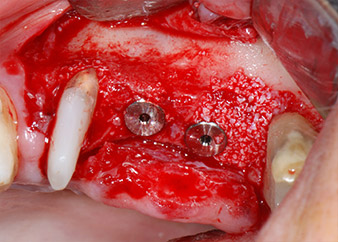

Implant beds were prepared at sites 25 and 26 with rotary instruments, used in a contra-angle handpiece with a 20 : 1 transmission ratio with an updated powerful implant motor (Implantmed, W&H) (Fig. 8).

The implants (Restore, Keystone Dental, diameter 3,75 mm, length 8.0 mm) were placed with the implant motor

(Figs. 11 and 12).

Low speed insertion of implant 26

Fig. 11: Low speed insertion of implant 26 with a torque limitation of 35 Ncm.

ready for the cover screws

Fig. 12: Both implants in place and ready for the cover screws.